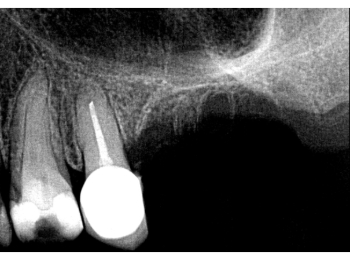

Röntgen Langzeitprovisorium

15: Zustand mit Langzeitprovisorium nach Ausheilung nach Revision.